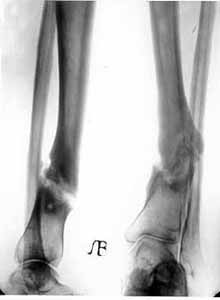

False joint of lower/third of shinbone.

Results of treatment.